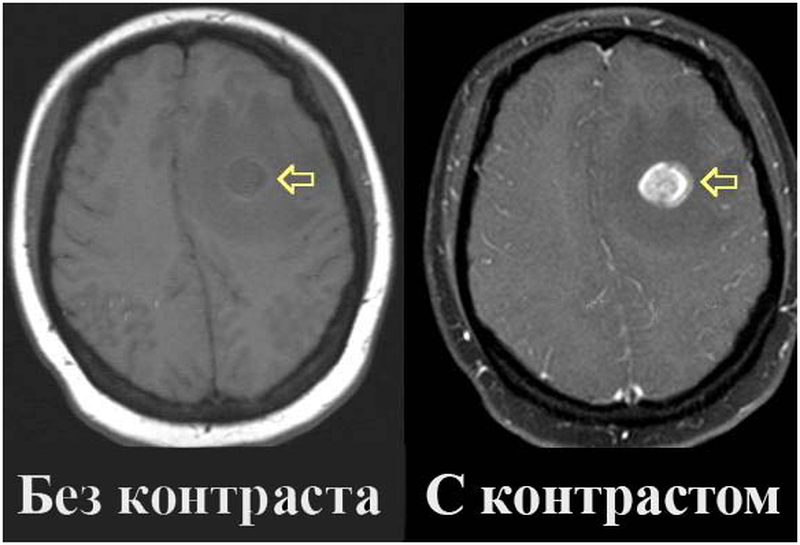

Карциноид червеобразного отростка гистология. Карциноид кишечника гистология. Карциноид червеобразного отростка патанатомия. Карциноидная опухоль микропрепарат. Мрт головного мозга с контрастированием. Мрт с контрастированием опухоль. Мрт головы с контрастом. Магнитно резонансная томография с контрастом головного мозга.

Мрт головного мозга с контрастированием. Мрт с контрастированием опухоль. Мрт головы с контрастом. Магнитно резонансная томография с контрастом головного мозга. Классификация опухолей. Классификация новообразований. Классификация опухолей по воз. Классификация воз опухолей костей.